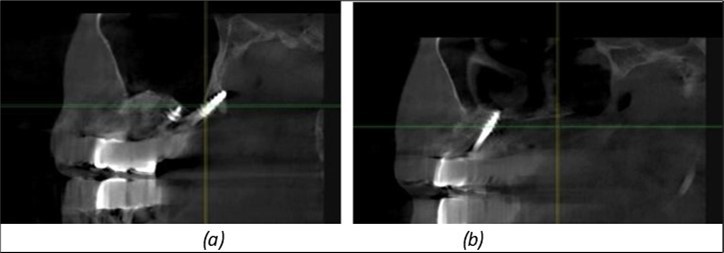

Figure 12.Implants fixed distally in quadrant 4 with fixation at the level of the mylohyoid line: (a) The most distal implant fixed in unaffected bone from the previous restoration; (b) The implant fixed in the area where the two stage implant was removed.

Figure 13.Corticobasal BCS implants fixed between the vestibular and lingual cortices with support on the basal bone: (a) BCS fixed between the lateral cortices; (b) BCS implant with support on the basal cortex.